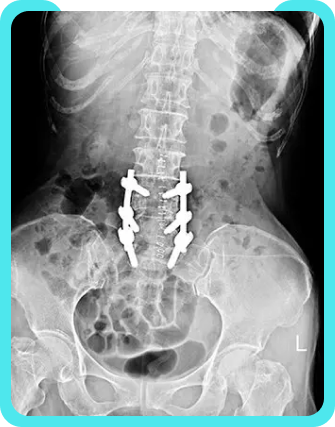

Post Laminectomy Syndrome

What is Post-Laminectomy Syndrome?

Are you seeking a pain management doctor in Bangalore? You could be seeking one due to surgery which has failed to reduce or eliminate back pain. Such a result is referred to as post-laminectomy syndrome (or ‘failed back syndrome’).

Typically, the nature of the pain experienced by patients with post-laminectomy syndrome correlates with the underlying pathology. One type of post laminectomy pain is neuropathic pain, which is caused initially by primary injury to the nervous system. In patients with post-laminectomy syndrome, the original spinal disorder that caused the nerve injury prior to surgery may cause neuropathic pain to return. Another type of pain that may persist after back surgery is radicular pain, or shooting pain that travels along the dermatome or sensory distribution of a nerve due to inflammation or other irritation of the nerve root. Initially, nerve root irritation may arise from a spinal disc herniation, or torn or bulging disc. Eventually, neuropathic and radicular pain can result in central sensitization of nervous tissues, or harmful changes to pain receptors. Treatments for this syndrome can range from medication and physical therapy, and even additional surgery if the pain is too great. It is crucial to seek a pain management doctor because an accurate diagnosis is imperative. A precise diagnosis is necessary to facilitate an effective plan of treatment. An evaluation may include x-rays, MRIs, EMGs, and other means of identification. After identifying the source of your ailment, a treatment plan can be prescribed and implemented.